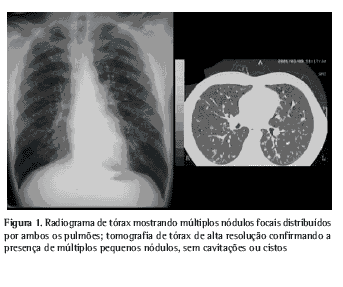

O radiograma de tórax mostrou múltiplos nódulos focais em ambos os pulmões. A tomografia computadorizada de alta resolução confirmou a presença desses pequenos nódulos, sendo o maior de 10 mm de diâmetro. As lesões localizavam-se predominantemente em lobos superiores mas, com menor extensão, distribuíam-se também pelos campos pulmonares médios, poupando as bases e os ângulos costo-frênicos. Cistos e cavitações nesses pequenos nódulos não foram encontrados. Não se detectaram adenomegalias (Figura 1).